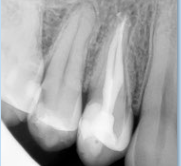

牙髓神经是慢性坏死,患者通常没有明显的主观疼痛,但是牙齿的颜色逐渐变黑、变暗,并且根尖周有局部的胀痛,或者在进行X片检查的时候,发现根尖周出现了慢性的炎症。

根管治疗的确是比较复杂,使用的器械多,并且需要经过多个治疗步骤,和拍摄多张X光片,才能完成整个治疗过程。